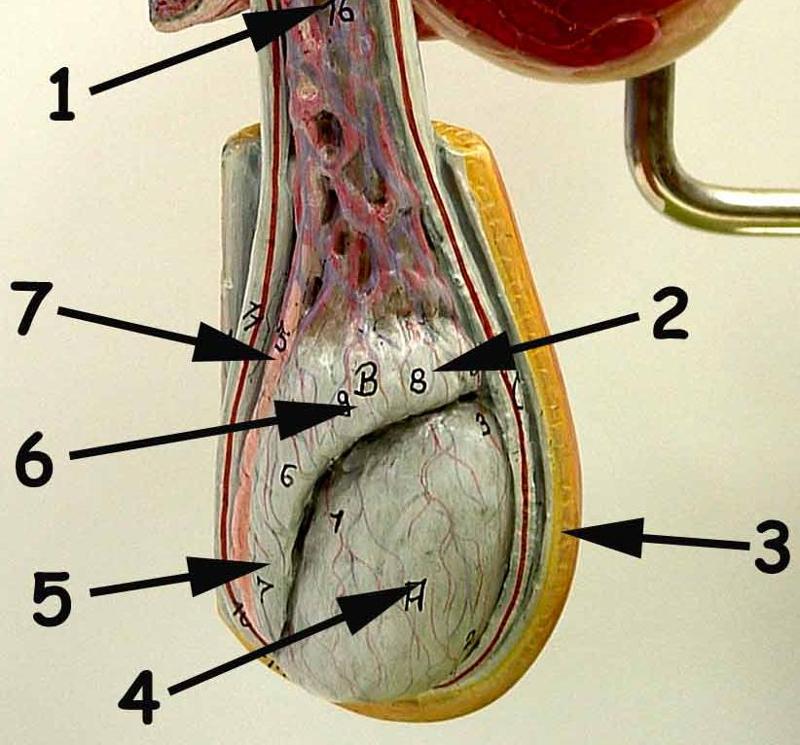

Cremaster muscle

Epididymis

Scrotum

Seminiferous tubule

Spermatic cord

Testis (s.) Testes (pl.)

Vas deferens (=ductus deferens)